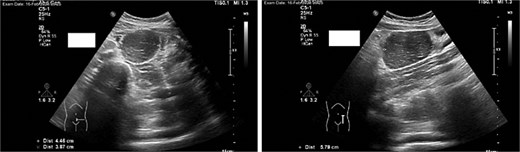

Imaging studies included abdomen/KUB X-ray was unremarkable (Fig. 1). An abdominal ultrasound, which showed a hypoechoic mass in the left lower abdomen and minimal free fluid (Fig. 2). A computed tomography (CT) scan of the abdomen revealed an appendicular abscess and a soft tissue mesenteric mass measuring 6 × 4 cm (Fig. 3).

An abdominal ultrasound, which showed a hypoechoic mass in the left lower abdomen, and minimal free fluid.